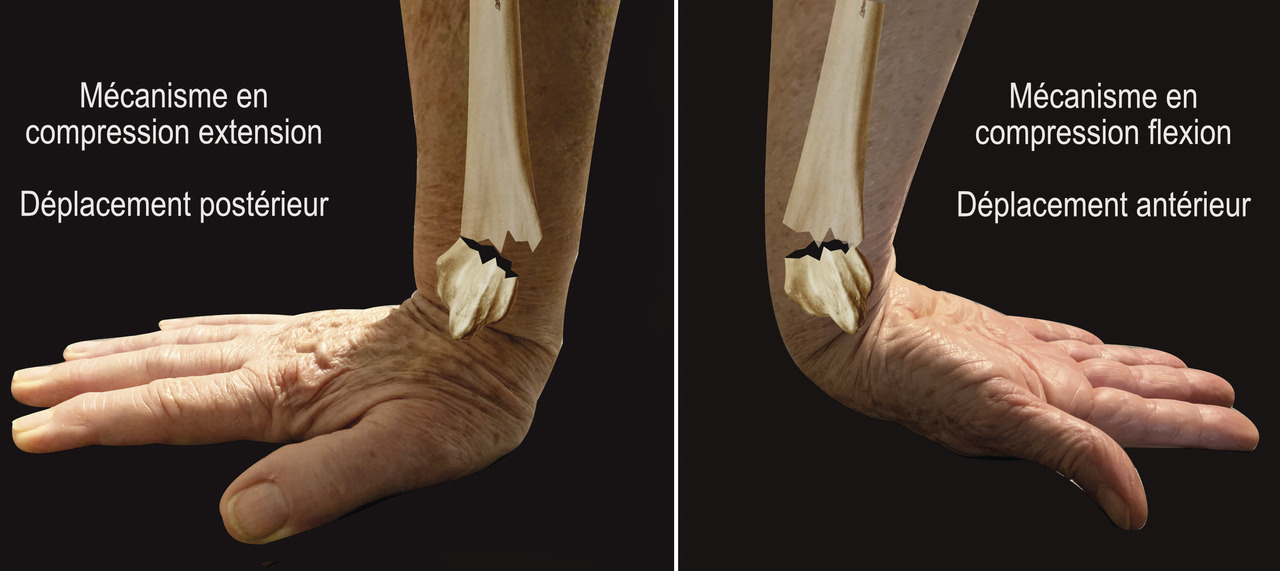

Au niveau métaphysaire le déplacement peut être postérieur ou antérieur (fig. 6). En ce qui concerne le déplacement postérieur, il est important de se souvenir que la surface articulaire regarde vers l’avant. En d’autres termes, dès que cela n’est plus le cas, même si la surface articulaire n’est pas orientée vers l’arrière, il s’agit d’un déplacement postérieur. Classiquement, le déplacement postérieur est lié à un mécanisme dit en compression-­extension, c’est-à-dire une chute sur la main, le poignet étant en extension (fig. 7). Le déplacement est dit antérieur s’il y a une exagération de l’orientation antérieure de l’épiphyse radiale. Ce déplacement est classiquement lié à un mécanisme dit en compression-flexion, c’est-à-dire une chute sur la main, le poignet étant en flexion (fig. 7). La plupart du temps, ce déplacement postérieur ou antérieur s’accompagne également d’un déplacement externe, avec un tassement au niveau de la corticale latérale (fig. 8). Outre le déplacement antérieur, postérieur ou latéral, il est très important d’analyser au niveau du foyer de fracture métaphysaire l’importance de la comminution qui peut être uniquement postérieure, ou antérieure, ou circonférentielle, ce qui conditionne la stabilité de la fracture et oriente vers le type d’ostéosynthèse à réaliser.